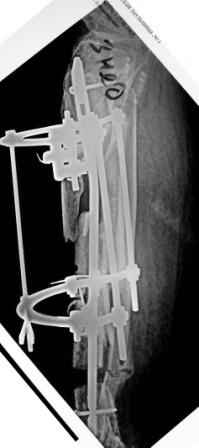

Коллеги!Позвольте продолжить обсуждение темы «ложный сустав левой голени.» Больной К 45 лет, начало см. http://www.weborto.net/forum/1228422607/ И рассказать о результатах проделанной работы. Остановились на следующей тактике 1) Наложить Аппарат Илизарова. В аппарате восстановить оси трех смещенных относительно друг-друга фрагментов большеберцовой кости. Устранить вальгусную деформацию дистального отдела большеберцовой кости. Что и было выполнено. - Была выполнена репозиция в аппарате (рис1) 2) После репозиции более очевидна стала проблема дефекта кости в верхней трети голени, два фрагмента свободно лежат. Остановились на варианте перехода на интрамедуллярный синтез стержнем с покрытием костный цемент+ванкомимцин и замещении дефекта с помощью транспорта фрагмента (рис 2) 3) Третьим этапом наложили модуль на промежуточный фрагмент.(рис 3) И начали его транспорт на стержне в проксимальном направлении. (рис 3 а) Надеемся что «вырастет» регенерат в дистальном отделе, а в проксимальном отделе фрагмент «упрется» и прирастет. Хочу сказать слова благодарности за обсуждение на форуме этого случая. Особые слова благодарности Иванову Павлу Анатольевичу!!! Он помогал Словом, а самое главное делом. Приезжал, оперировал! За что ему нижайший поклон! С ув Коробушкин Г